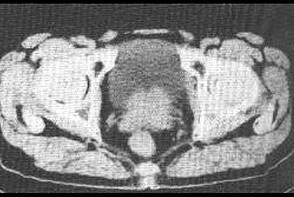

问题 良性前列腺增生需与前列腺癌鉴别时,可进行以下哪项检查 ( )

选项 A、前列腺特异性抗原 B、膀胱造影 C、残余尿量 D、有无血尿 E、发病年龄、排尿困难程度

答案 A